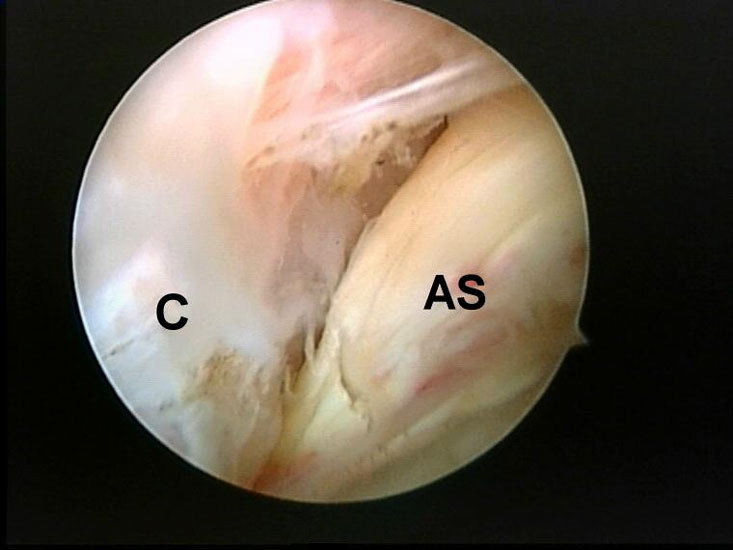

Abbildung 5-7, Video 2

Zunächst wird die Bursektomie (Abb. 5: gerötete Bursa subachillea; C=Calcaneus, B=Bursa, AS=Achillessehne) mit der Radiofrequenzsonde durchgeführt und die Haglundexostose dargestellt. Alternativ kann die Bursektomie mit einem Shaver durchgeführt werden. Hierbei sollte der Ansatz der Achillessehne kaudal einsehbar sein (Abb. 6: C=Calcaneus, AS=Achillessehne) und unbedingt die gesamte mediolaterale Ausdehnung der posterioren Calcaneusfläche erfasst werden (Abb. 7). Häufig liegen Anteile der Exostose weit medial und/oder lateral und werden übersehen.